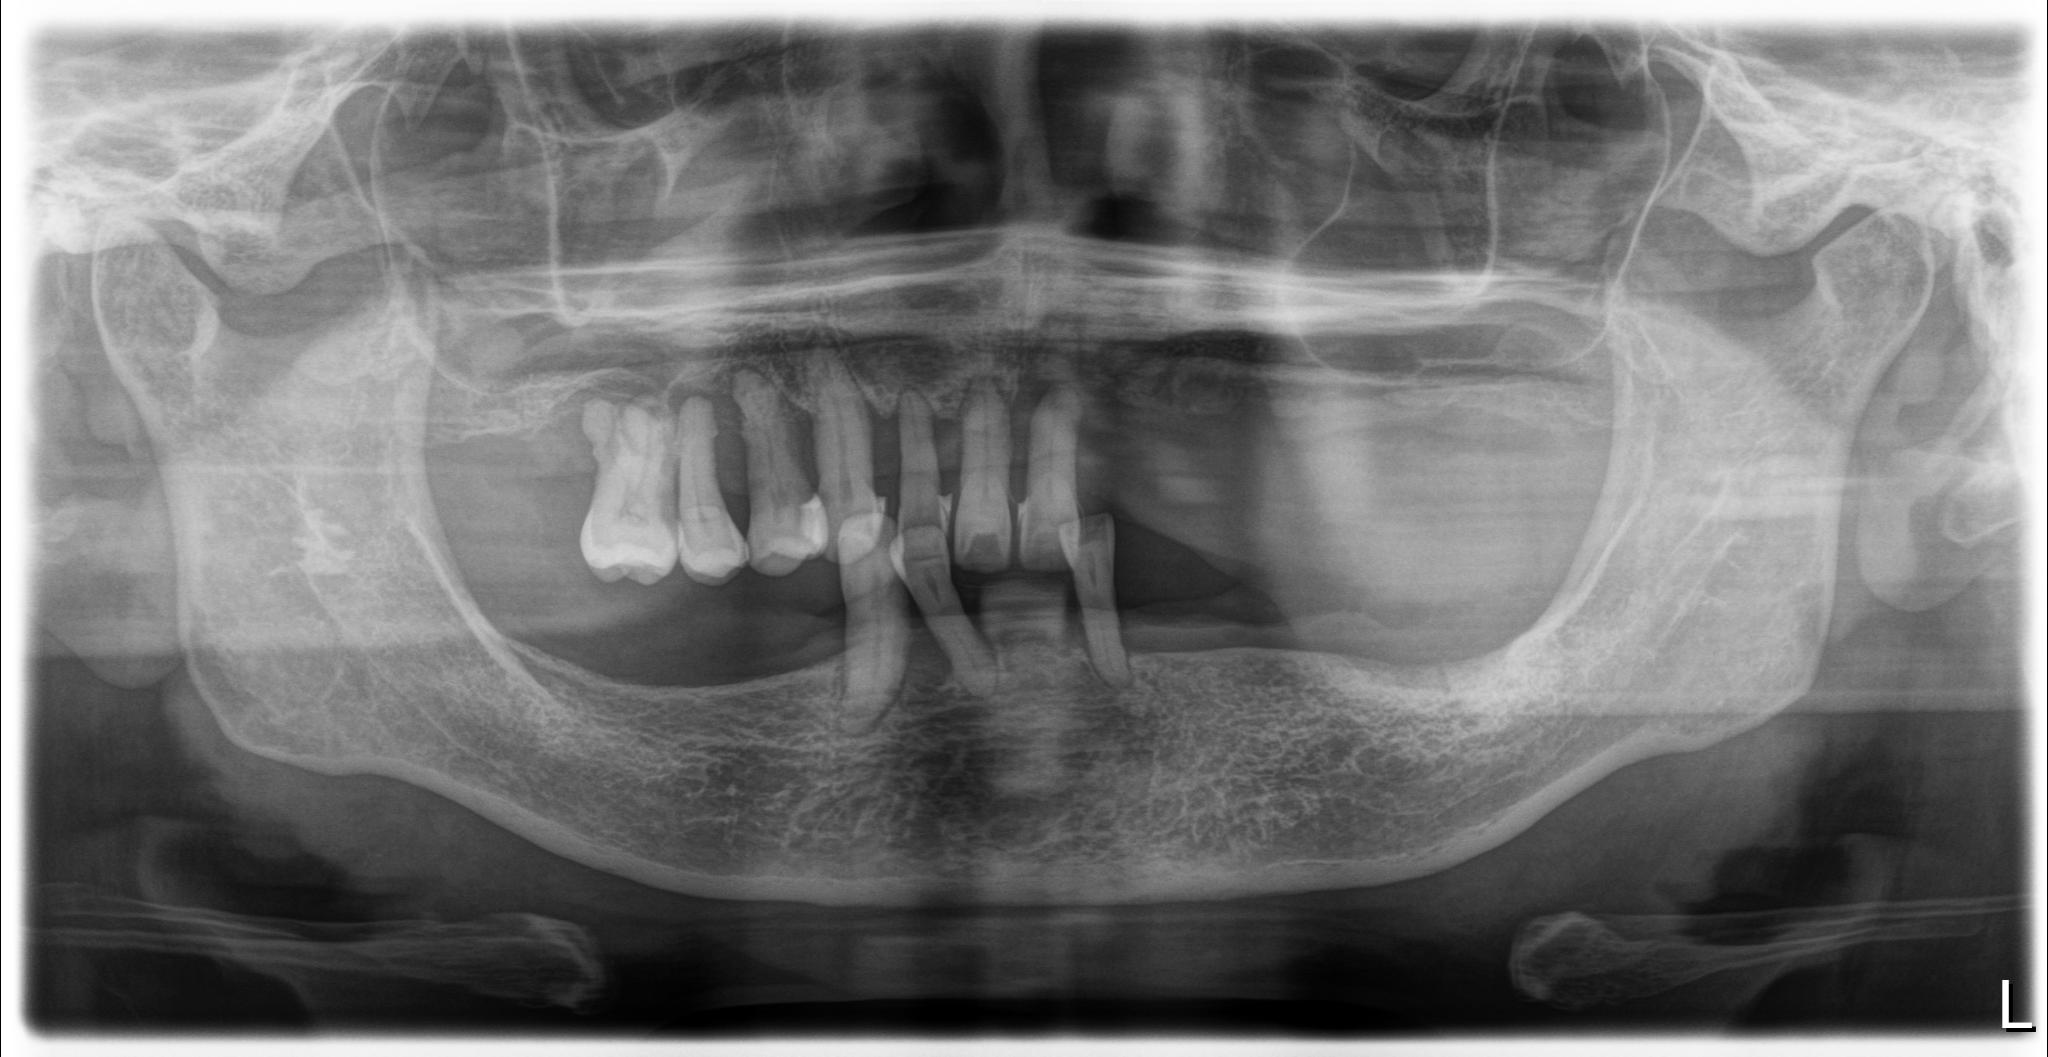

術前

内容 :上下顎オールオン4ザイゴマ2

費用 :5,552,800円

※モニター価格

期間 :半年

リスク:出血・腫れ・痺れ・痛み